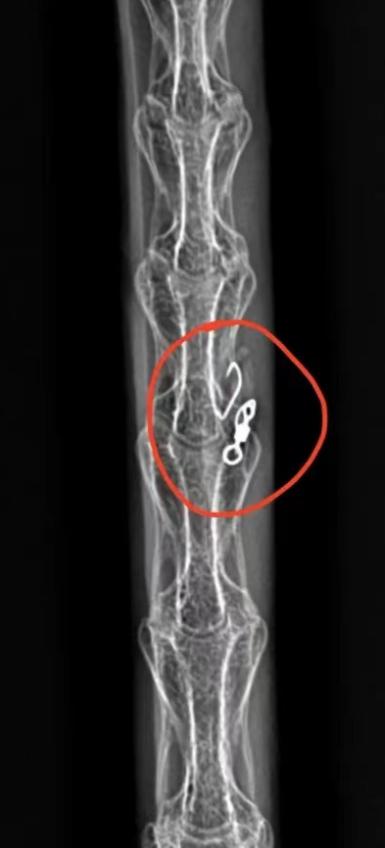

爱宝嘴上的鱼钩

今年4月21日下午4时许,郑州北龙湖水务保安在巡逻中发现天鹅“爱宝”的嘴上有鱼钩,经工作人员和志愿者齐心合力救援,最终用网枪才将“爱宝”抓住。控制住“爱宝”后,救助人员发现它嘴上挂有3个鱼钩,后经X光检查,“爱宝”食管内还有一个鱼钩。在大家的努力下,这些鱼钩都被清除了。

爱宝食管中的鱼钩